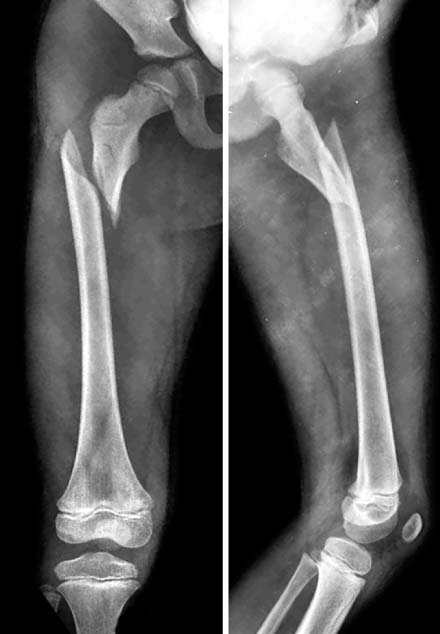

Fig. 7

A proximal femoral fracture in 7 years-old boy. In this fracture, the proximal fragment usually abducts and rotated externally. It makes the reduction very difficult. In the past, open reduction with the plate was commonly used.

jkfs-21-169-g007.jpg

Fig. 8

With flexible nails, the reduction was achieved. Then, the plate was fixed in the MIPO method.